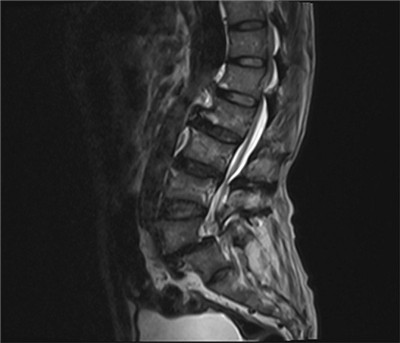

患者张某,男,69余,患者以“腰痛伴双下肢抽痛5年,摔伤后加重伴行走困难6天”在当地诊断为腰椎滑脱伴椎管狭窄(图1),转入我科拟行手术治疗,入院后完善检查,发现患者有广泛严重的胸椎黄韧带骨化伴不全瘫(图2),钙化范围涉及了胸2至腰2节段,且很多节段压迫极其严重(图3),原本相当于大拇指粗细的椎管,被钙化的黄韧带硬生生挤成了一条缝。

图1 腰椎MRI